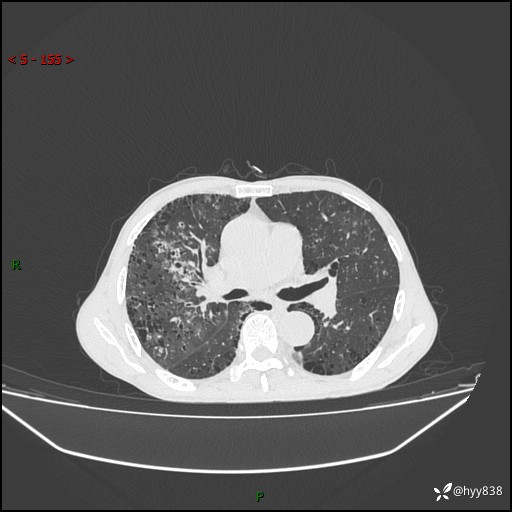

胸部CT平扫